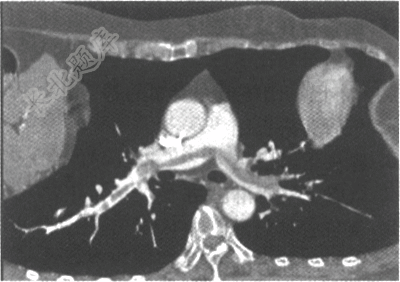

- 单项选择题女性患者,52岁。呼吸困难1个小时。CT肺动脉造影如下图,应诊断为

E、急性肺动脉栓塞